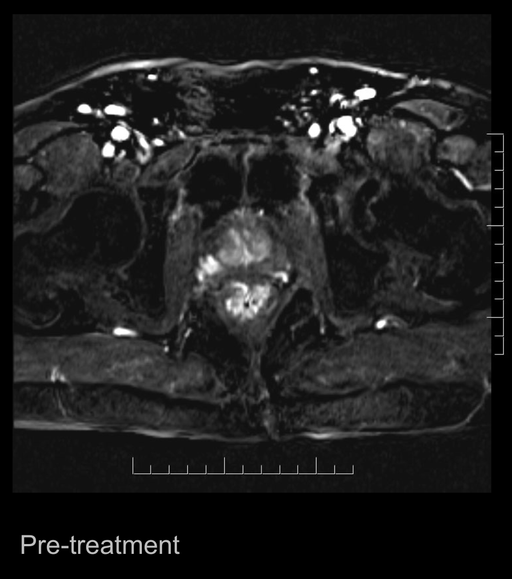

The company has previously announced that the last treated patient prior to treatment had a PSA value of 4.9 ng/ml and, upon revisiting after treatment, the value had fallen to 0.3 ng/ml, indicating that the cancer tumour was eradicated. At the lecture, Johannes Swartling showed images from the MRI scans that were made before and after treatment. These MRI images in combination with the measured changes in the PSA value represent a clear indication that the tumour has been eradicated and that the treatment has achived the intended effect.

The images are appended with this press release.